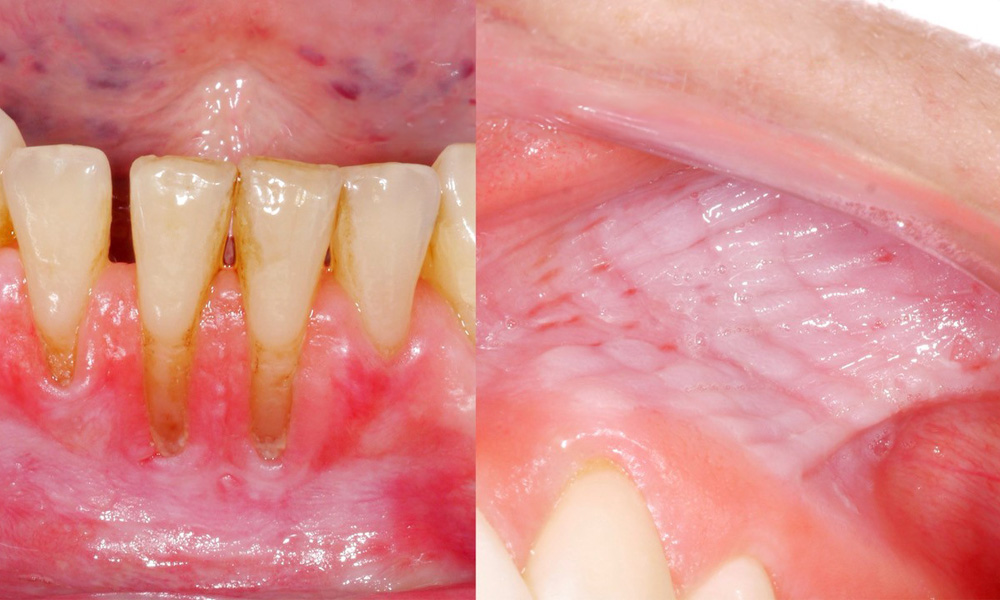

Snus verursacht Schleimhautläsionen & Gingivarezessionen

Es zeigte sich im Rahmen der klinischen Untersuchung, dass der regelmäßige Konsum von Snus folgende Auswirkungen auf die Mundschleimhaut haben kann:

- Ca. 80 % der Untersuchten, die täglich Snus konsumieren, wiesen Snus-induzierte Schleimhautläsionen auf.

- Jede zusätzliche Dose Snus, die pro Monat konsumiert wurde, stieg das Risiko für eine schwerere Schleimhautläsion signifikant an.

- Ca. 20 % der Untersuchten, die täglich Snus konsumieren, wiesen Snus-induzierte Gingivarezessionen auf.

- Für jedes weitere Jahr, in dem Snus bereits konsumiert wurde, stieg das Risiko für Snus-induzierte Gingivarezessionen signifikant an.